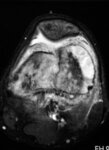

Ressonância nuclear magnética (RNM), incidência axial; osteossarcoma do fêmur distal mostrando sinal de alta intensidade; imagem ponderada em T2

Do acervo do Dr. Michael J. Klein e da Dra. Luminita Rezeanu